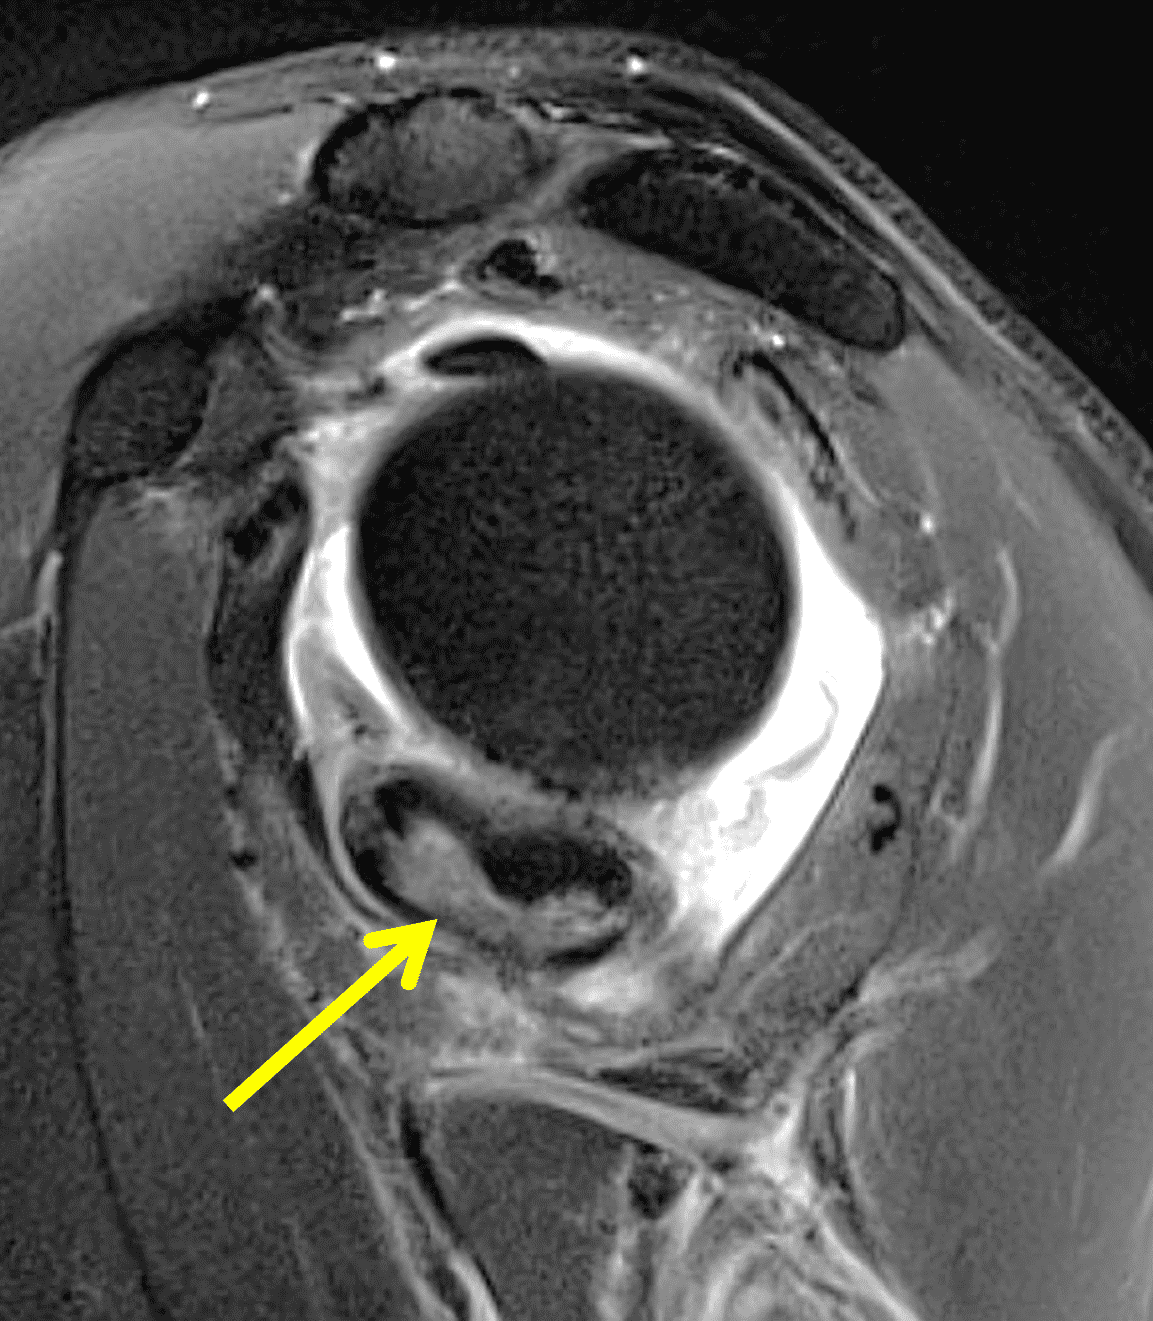

Figure 4: Secondary osteochondromatosis (loose bodies) in the shoulder joint. An axial fat-suppressed T2-weighted image shows multiple intra-articular bodies of variable size (red arrows) and severe glenohumeral cartilage (yellow arrows) due to osteoarthrosis.

Figure 2: An ill-defined, infiltrative mass superficial to and involving most of the distal quadriceps tendon (red arrows) has intermediate signal on the fat-suppressed fluid-sensitive (2A) and proton density-weighted (2B) images, with faint marrow edema in the adjacent patella (yellow arrow).